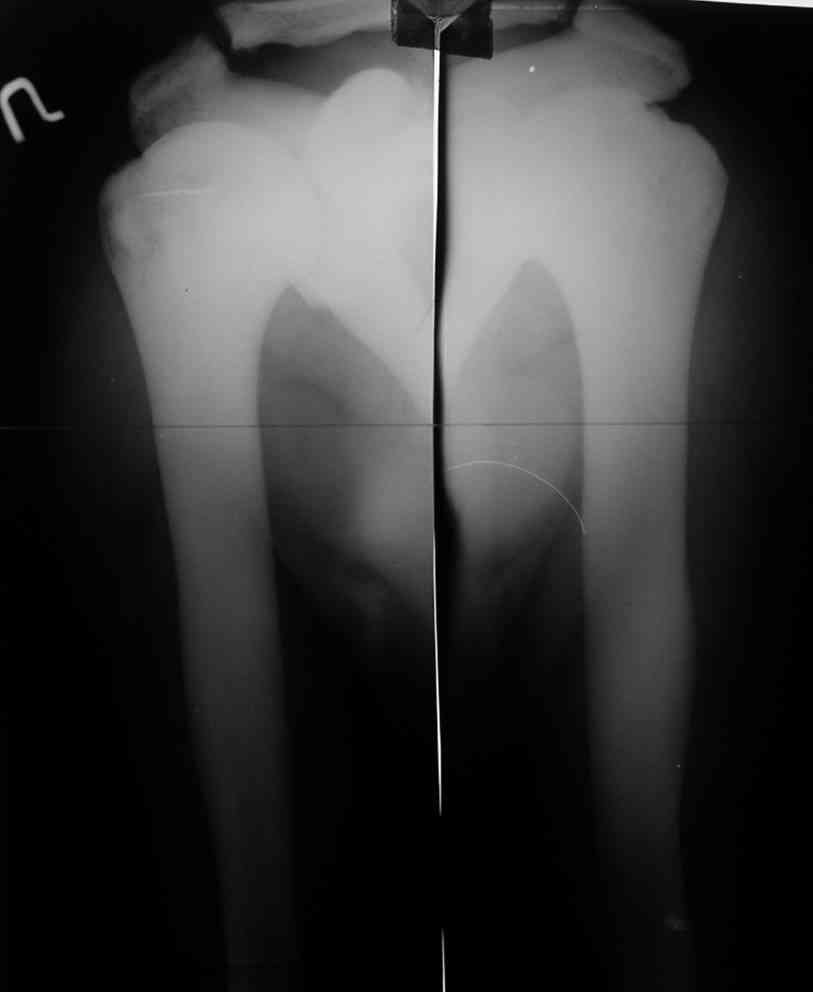

Уважаемый Константин Иванович! Полностью согласен с проф. Михайловым, данный случай не похож на мраморную болезнь, при которой имеется резкое, строго симметричное и генерализованное уплотнение костной ткани (остеопетроз), и кость оказывается построенной преимущественно из гомогенного компактного костного вещества. Для примера привожу случай из архива нашего института (бедренные, плечевые кости и таз, рис 1,2,3)